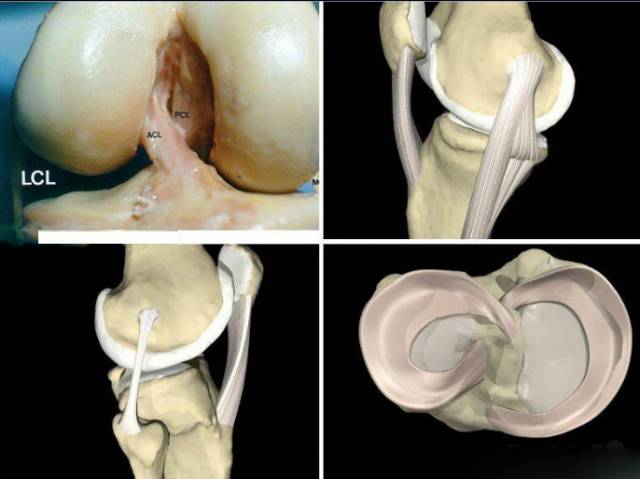

13 韧带损伤

侧副韧带损伤

内侧副韧带损伤

外侧副韧带(外侧韧带复合体)损伤

交叉韧带损伤

前交叉韧带损伤

后交叉韧带损伤

韧带的复合损伤

14 半月板损伤